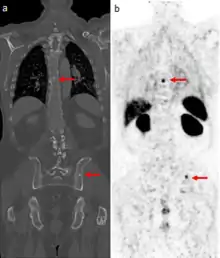

Gallium DOTA scans

68Ga DOTA conjugated peptides (including 68Ga DOTA-TATE, DOTA-TOC and DOTA-NOC) are used in positron emission tomography (PET) imaging of neuroendocrine tumours (NETs). The scan is similar to the SPECT octreotide scan in that an octreotide-based somatostatin analogue (such as edotreotide) is used as the radioligand, and there are similar indications and uses as ocreotide scans, however image quality is significantly improved.[35] Somatostatin receptors are overexpressed in many NETs, so that the 68Ga DOTA conjugated peptide is preferentially taken up in these locations, and visualised on the scan.[36] As well as diagnosis and staging of NETs, 68Ga DOTA conjugated peptide imaging may be used for planning and dosimetry in preparation for lutetium-177 or yttrium-90 DOTA therapy.[37][38]

Gallium-68 DOTA scans are increasingly replacing octreotide scans (a type of indium-111 scan using octreotide as a somatostatin receptor ligand). The gallium-68 is bound to an octreotide derivative chemical such as DOTATOC and the positrons it emits are imaged by PET-CT scan. Such scans are useful in locating neuroendocrine tumors and pancreatic cancer.[7][8]